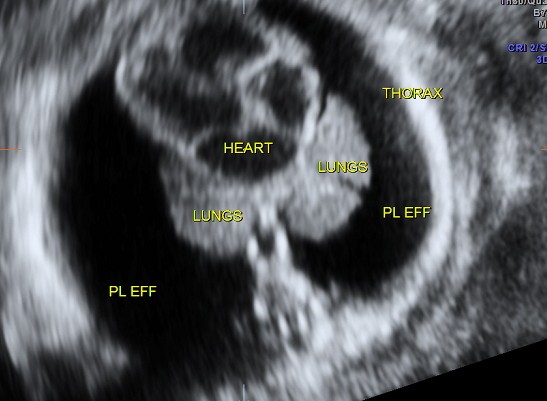

NON IMMUNE HYDROPS – RH ISO IMMUNISATION HAS BEEN RULED OUT .

THIS FETUS SHOWED SEVERE SUB CUTANEOUS EDEMA ,BILATERAL PLEURAL EFFUSION AND ASCITES .

PATHO-PHYSIOLOGY IN SHORT IS INCREASED CVP.

CAUSES COULD BE CHROMOSOMAL,CARDIOVASCULAR, PULMONARY, G.I ., G.U . ,HEMATOLOGICAL, INFECTIONS etc.